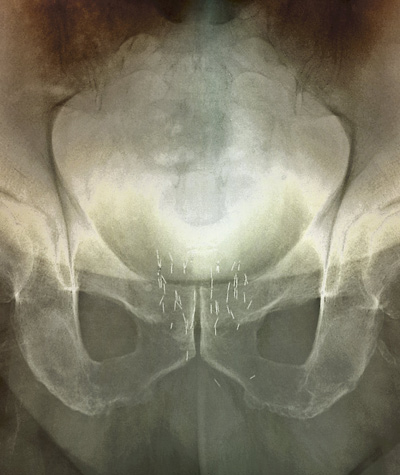

Illustrasjonsfoto: Science Photo Library